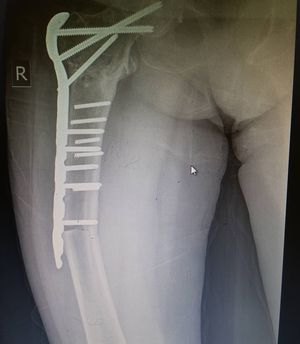

Osteoprotic patient with previous neck of the femur fracture presents to the hospital with a second fracture of the femur after just standing Up!!! the patient as you can tell is obese which caused extra stress on the bones thus this fracture ! @medicalcortex #medschool #medlife #hospital #openheartsurgery #medicine #medstudent #atrialfibrillation #thorax #nurse #doctor #perfusionist #heart #heartsurgery #surgery #operationroom #nursing #opcab #ablation #f4f #l4l #premed #usmle #surgeon #emergency #emergencyroom